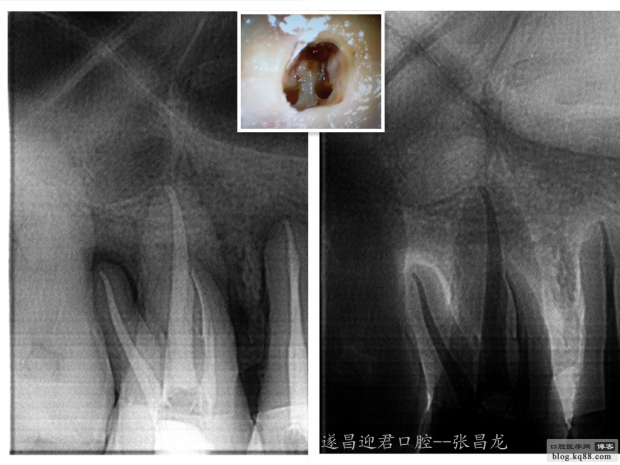

下面是我最近的一個(gè)患者,患者14,15,16均因楔狀缺損導(dǎo)致牙髓壞死,根管治療期間,16的近中頰根發(fā)生了斷針。

根充

根充前后X線片